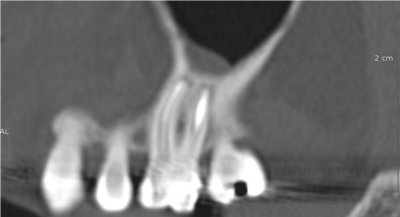

Le cone beam est une nouvelle technique de radiographie numérisée situé entre le panoramique dentaire et le scanner, il utilise un faisceau d’irradiation de forme conique d'où son nom. Cet appareil présente notamment l’avantage d’être plus précis que le panoramique dentaire et il possède une résolution similaire, voire supérieure à celle du scanner, avec en plus la possibilité d’une reconstruction numérique en 3D.

Il permet de balayer en un seul passage l’ensemble du volume à radiographier et en étant moins irradiant que le scanner.

Le cone beam utilisé en pathologie dentaire et maxillo-faciale est indiqué pour l’examen des tissus minéralisés (dents, cartilages, os), il permet d’identifier les lésions osseuses, les fractures, les infections, les kystes ou les corps étrangers.

Il évalue au plus juste le volume osseux et la position des structures anatomiques comme les nerfs en vue de la pose d’implants. La modélisation en 3D permet la taille et la forme des implants proportionnellement à la morphologie du patient et de simuler virtuellement leurs emplacements.